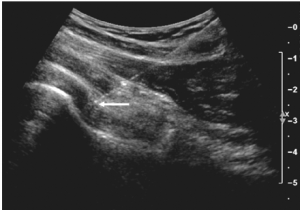

Dr. Domb and his team are highly trained in ultrasound-guided injections. These procedures are performed in the office at the time of your visit. The ultrasound machine assists Dr. Domb and his Physician Assistants to safely place injectable medications into or around the joint. Hip injection options include:

- Ultrasound Guided Injection